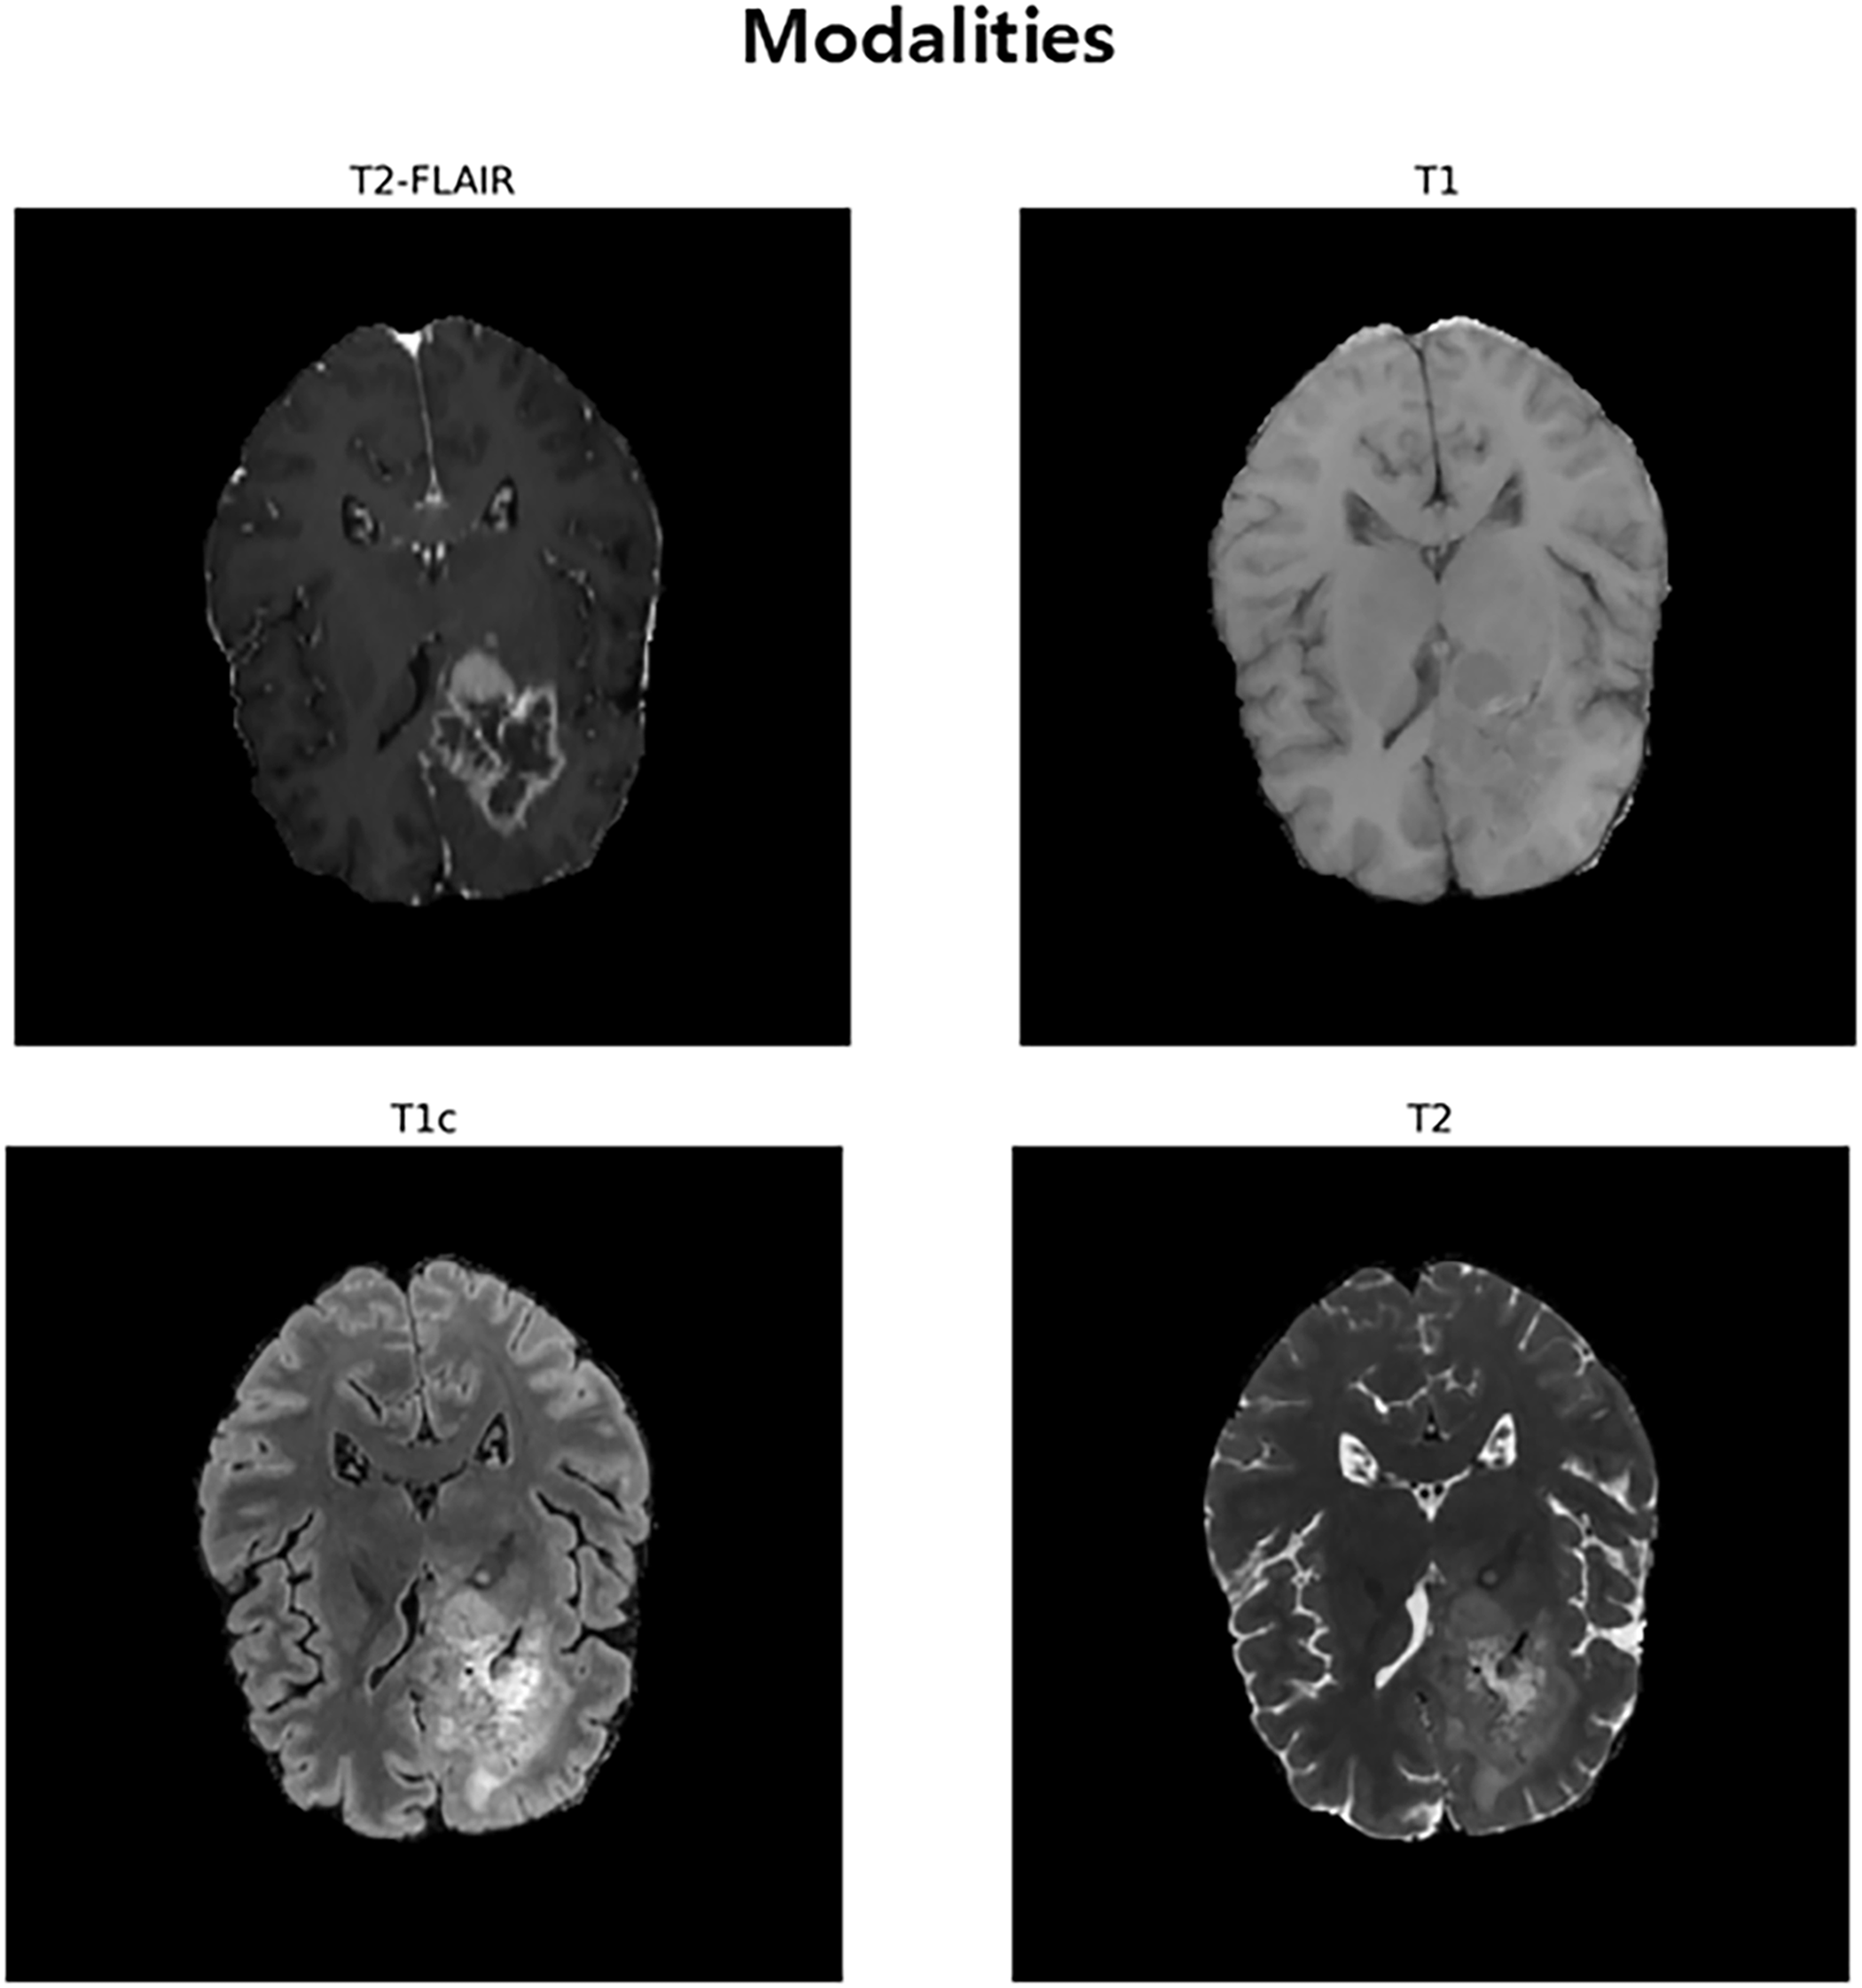

The experiments in this study used public brain tumor segmentation datasets BraTS2020, BraTS2021, BraTS2023, and BraTS2024. These datasets contain medical images of patients with gliomas and serve as standard references for evaluating the efficacy of models in medical artificial intelligence. Each dataset consists of multiple patient cases, and each case contains four types of 3D MRI sequences that are anatomically matched to each other. The included modalities are 1) T1-weighted (T1), 2) T1-weighted with contrast enhancement (T1c), 3) T2-weighted (T2), and 4) T2-weighted fluid-attenuated inversion recovery (T2-FLAIR), as shown in Fig. 1. These four images clearly show the characteristics of different lesions, such as the anatomical structure of the brain, active tumors identified through contrast enhancement, and edema around the tumor, enabling multi-modal analysis. All cases are provided with a correct answer segmentation mask labeled directly by the expert. The labels are divided into three major sub-regions that make up the tumor: necrotic (NCR) and non-enhanced tumor core (NET), peri-tumor edema (ED), and contrast-enhanced tumor (ET). Performance assessments are performed on three overlapping regions defined by combining these three labels: Whole Tumor (WT), Tumor Core (TC), and Contrast-Enhanced Tumor (ET). The scale of data used in this study included data from 369 patients for BraTS 2020, 1251 patients for BraTS 2021 and BraTS 2023, and 1621 patients for BraTS 2024. For our experiments, each dataset was randomly partitioned into training, validation, and test sets in a 70:10:20 ratio, respectively.

Figure 1: An Inter-Modal Comparison of MRI Sequences for Brain Tumor Visualization. This figure illustrates the use of four MRI sequences, T2-FLAIR, T1, T1c (post-contrast), and T2, for brain tumor segmentation. T2-FLAIR helps highlight peritumoral edema, T1 provides baseline anatomical details, T1c reveals contrast improved tumor regions, and T2 identifies tumor-associated fluid areas. Together, these modalities offer complementary information for accurate brain tumor identification and segmentation

The design of the HCAD block is centered on a channel-wise attention mechanism, and it is designed to directly address the challenges of multi-modal MRI-based segmentation. The input to our model comprises four distinct MRI sequences (T1, T1c, T2, and T2-FLAIR), each offering unique and complementary information critical for identifying different tumor sub-regions. For example, T2-FLAIR sequences excel at highlighting peritumoral edema, whereas post-contrast T1c scans are essential for delineating the active, enhancing tumor core. Our hypothesis is that an effective decoder must intelligently fuse these heterogeneous data streams. Therefore, instead of employing more generalized spatial-channel attention, HCAD focuses on learning the inter-channel relationships. By using the high-level feature map from the decoder as a contextual guide, the attention mechanism learns to dynamically modulate the influence of each modality-specific feature channel. This enables the model to, for instance, assign greater weight to features derived from the T1c channel when reconstructing the enhancing tumor boundary, while relying more on T2-FLAIR features for the whole tumor region. This targeted, modality-aware approach allows for a sophisticated yet computationally efficient feature fusion, making it a highly effective strategy for this specific task.